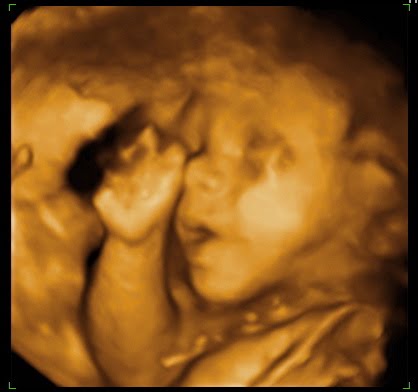

- הפנים (ארובות עיניים ושפתיים בלבד)

- ארובות העיניים ושפתיים